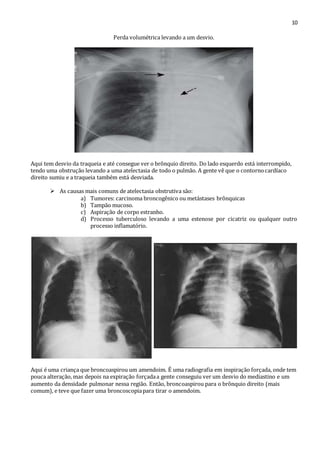

Perda volumétrica levando a um desvio.

Aqui tem desvio da traqueia e até consegue ver o brônquio direito. Do lado esquerdo está interrompido,

tendo uma obstrução levando a uma atelectasia de todo o pulmão. A gente vê que o contorno cardíaco

direito sumiu e a traqueia também está desviada.

 As causas mais comuns de atelectasia obstrutiva são:

a) Tumores: carcinoma broncogênico ou metástases brônquicas

b) Tampão mucoso.

c) Aspiração de corpo estranho.

d) Processo tuberculoso levando a uma estenose por cicatriz ou qualquer outro

processo inflamatório.

Aqui é uma criança que broncoaspirou um amendoim. É uma radiografia em inspiração forçada, onde tem

pouca alteração, mas depois na expiração forçada a gente conseguiu ver um desvio do mediastino e um

aumento da densidade pulmonar nessa região. Então, broncoaspirou para o brônquio direito (mais

comum), e teve que fazer uma broncoscopia para tirar o amendoim.